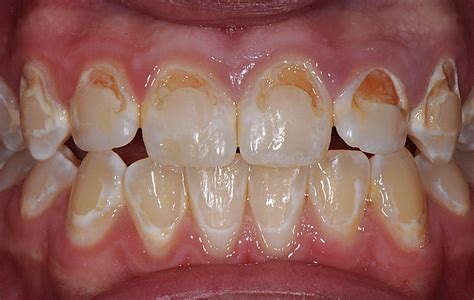

Recognizing the signs of tooth decay front teeth problems early can save you from invasive dental procedures. The process typically begins with white spots, which indicate demineralization, followed by brown or black spots as the decay deepens. Symptoms to watch for include:

- Visible white, yellow, or brown spots on the surface of the teeth.

| Stage 1: Enamel Decay | White spots | Fluoride treatment/Remineralization |

| Stage 2: Dentin Decay | Brown/Black spots | Composite resin fillings |